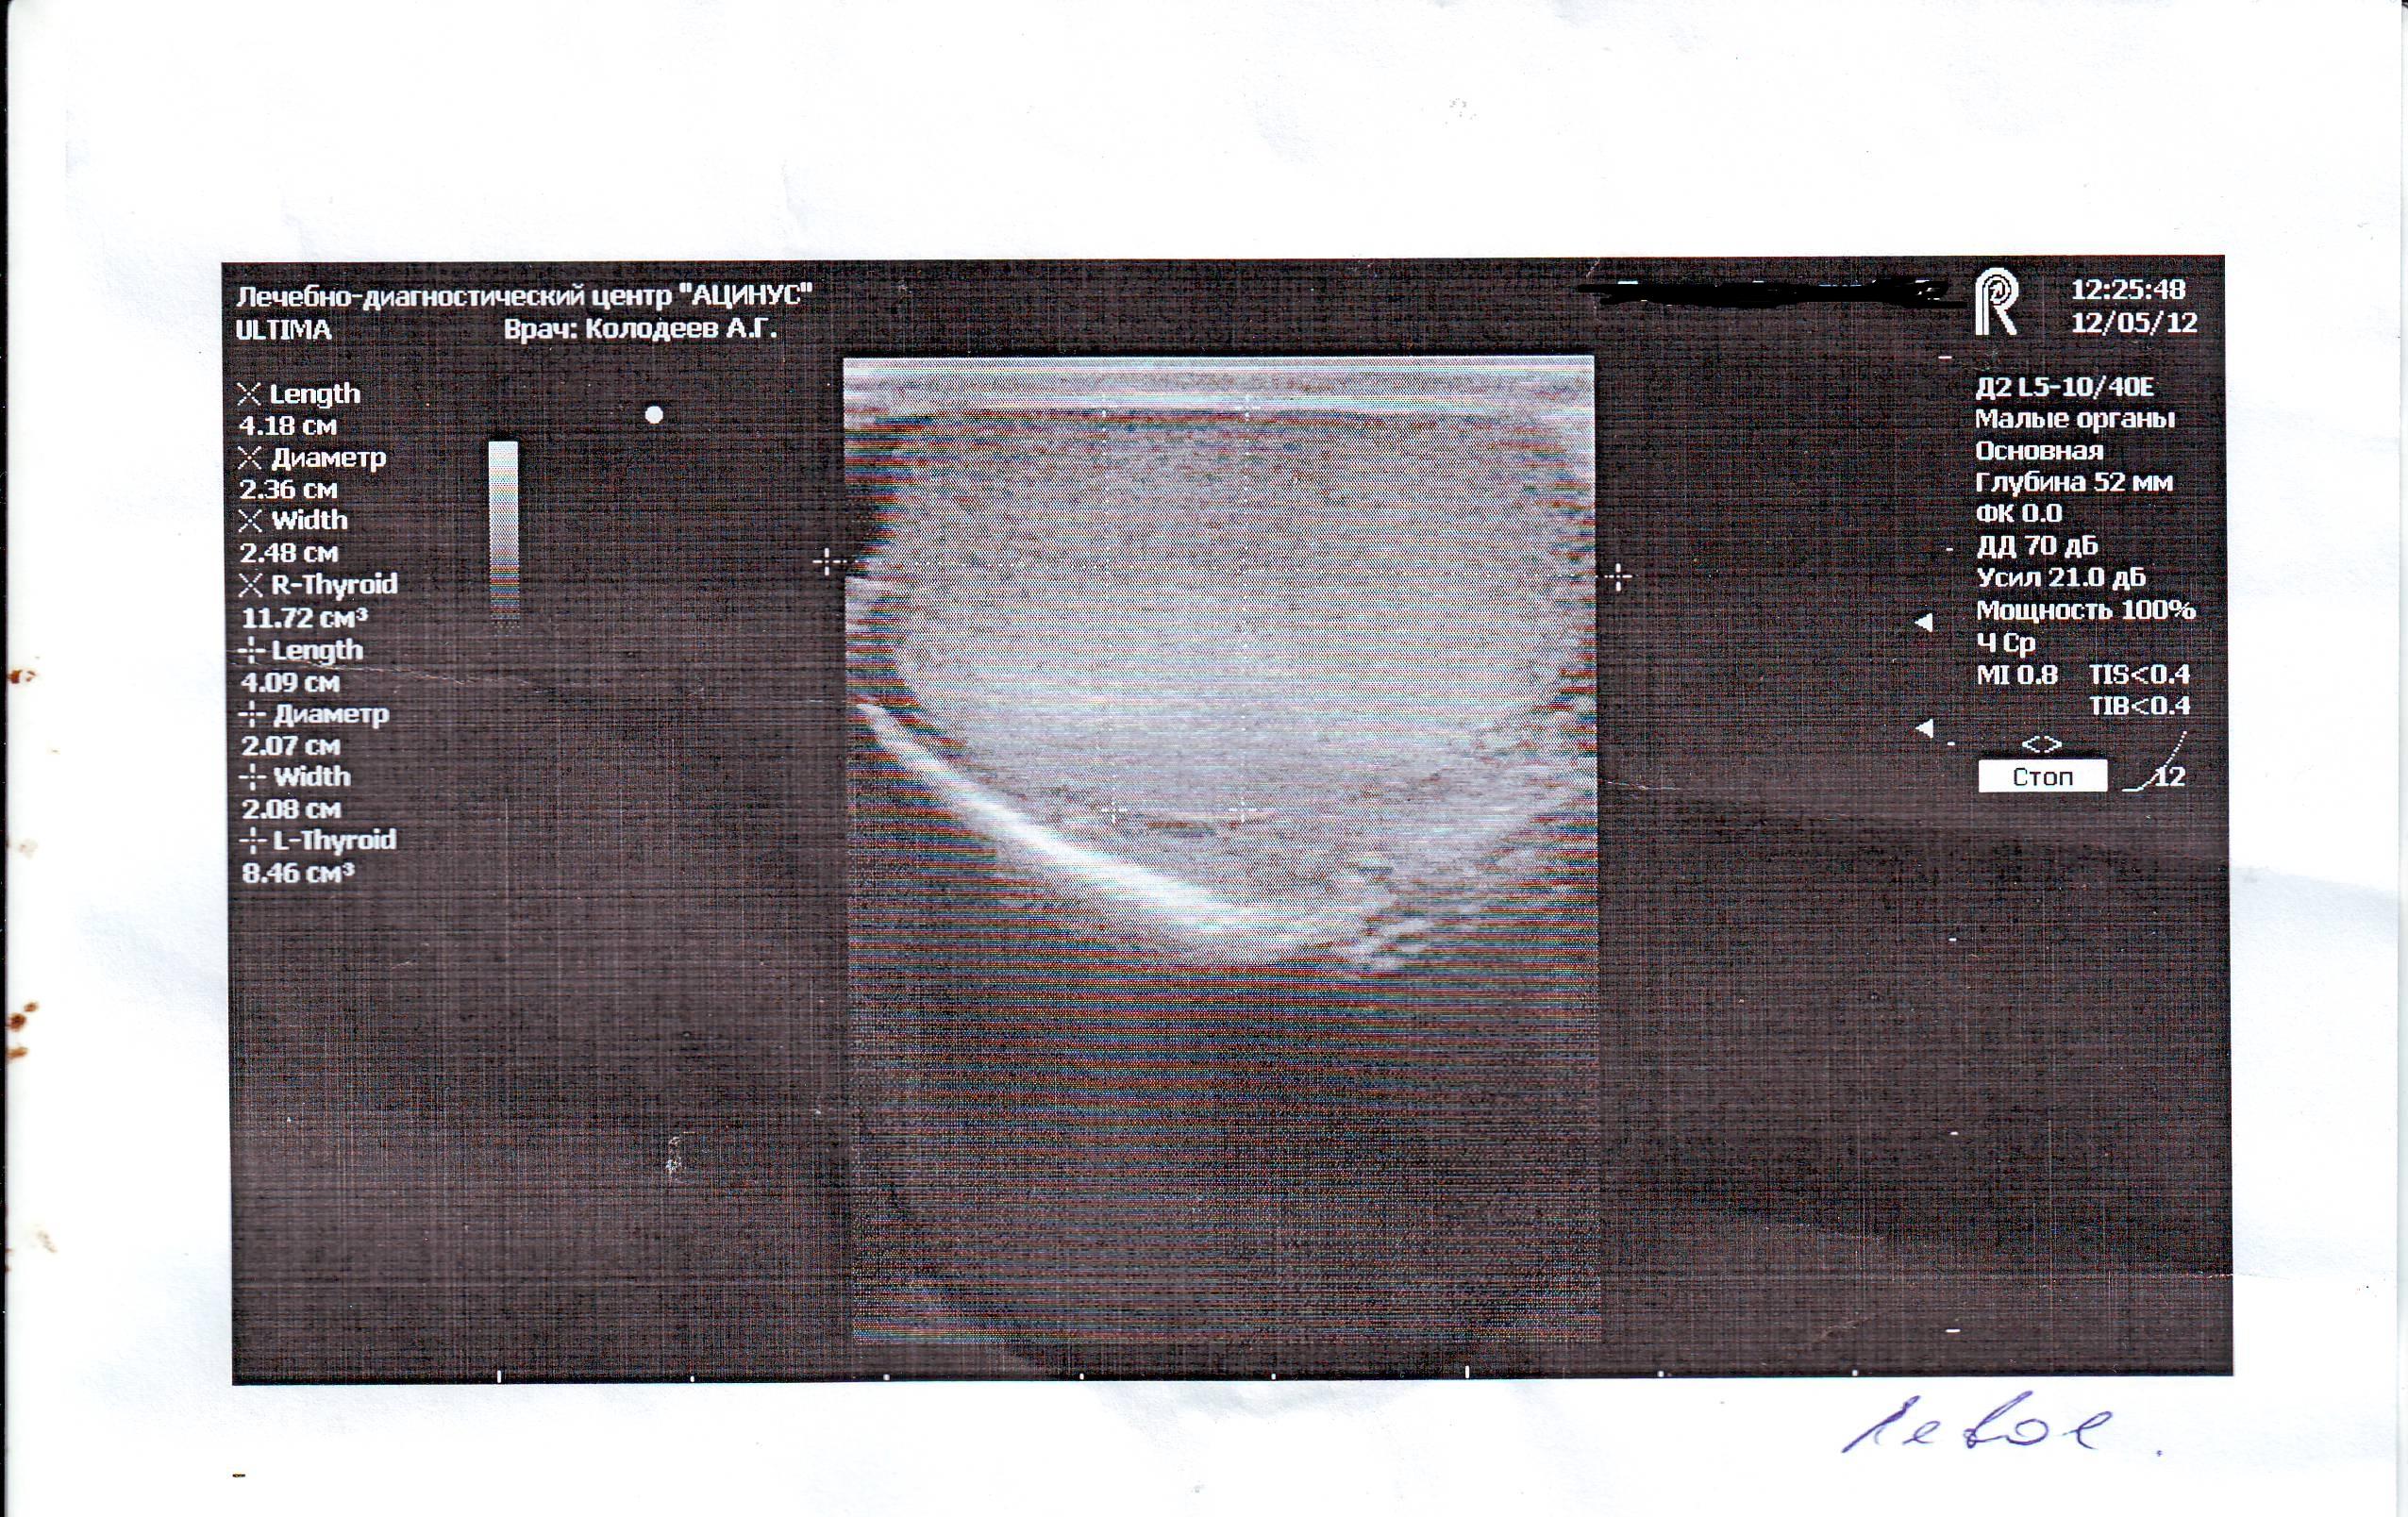

Здравствуйте у меня болели яички особенно левое пошёл к врачу сказал застой простаты, принимал препараты и заметил что яички уменьшились в размерах особенно левое и оно оттягиваеться иногда еще вниз сделал узи как указано в записи всё вроде хорошо так почему не пойму они уменьшились я так понял это атрофия яичек? можно ли восстановить размер?